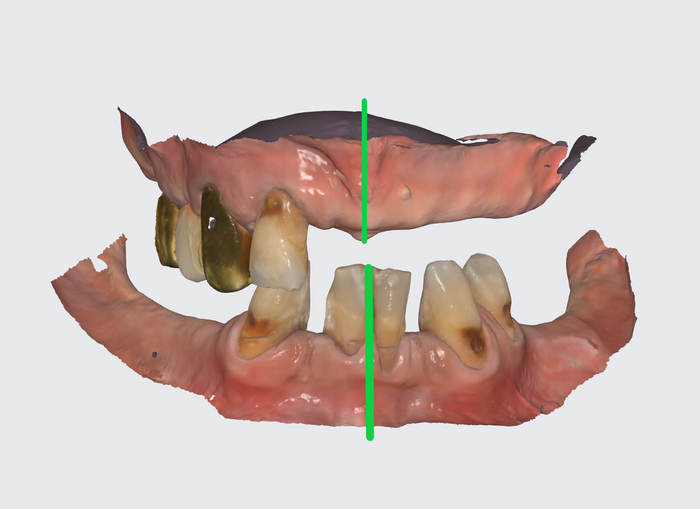

И так всё затянуто. Но то зуб на зуб не попадает, то губы не смыкаются:

Получилось так, что сверху всего 8 зубов, по 4 с каждой стороны. Чёрная точка (которую вы точно увидите, скос эмали на зубе 1.1) - конструктивные особенности, всё это будет закрыто пломбировочным материалом. Зуб 1.1 - дополнительный имлантат, который потом планируем убрать. Он нужен лишь для усиления, ибо торк полноценный был получен только на одном из остальных 6-ти установленных.

Так же важный момент - верхний протез соприкасается с нижним только в точках полученного торка (их всего 2), остальное "на весу" и жевать не способно.

Теперь посмотрим, как это выглядит во рту:

2 недели после тотальной работы на имплантатах - 2 челюсти

Шахты имплантатов закрыты временным материалом на 2 дня, он не очень эстетичный по цвету.